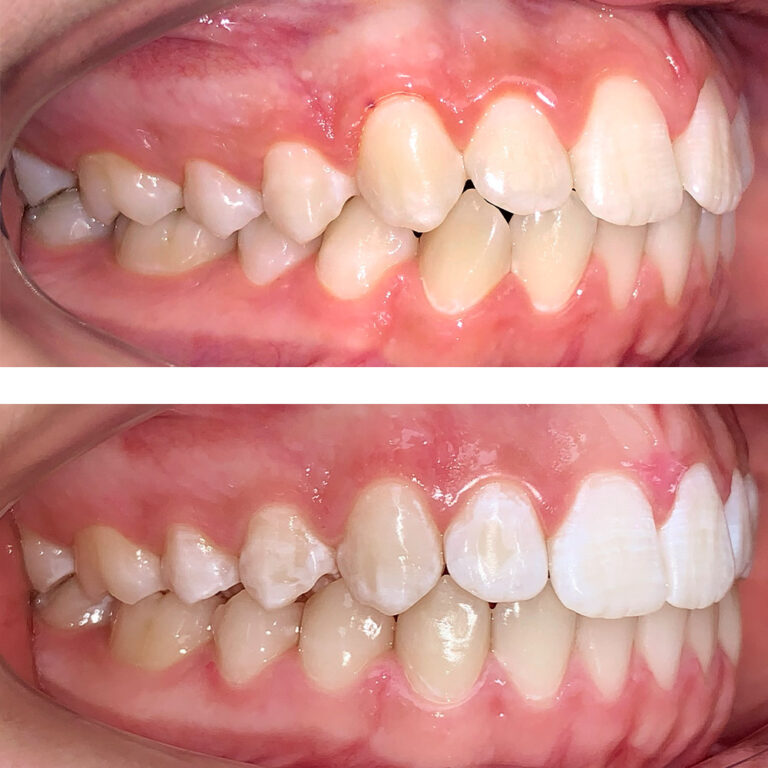

Кейс 16

Акинфиева

Количество кап ВЧ 20

Количество кап НЧ 20

ДО

ПОСЛЕ